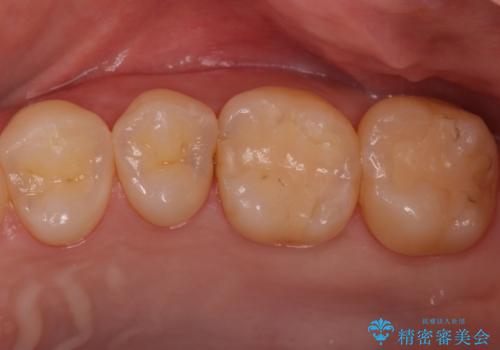

![[e-maxインレー] 矯正治療前の虫歯治療の症例 治療前](https://seimitsushinbi.jp/wp/wp-content/uploads/2023/08/IMG_1022-2-500x350.jpg?v=1691812242)